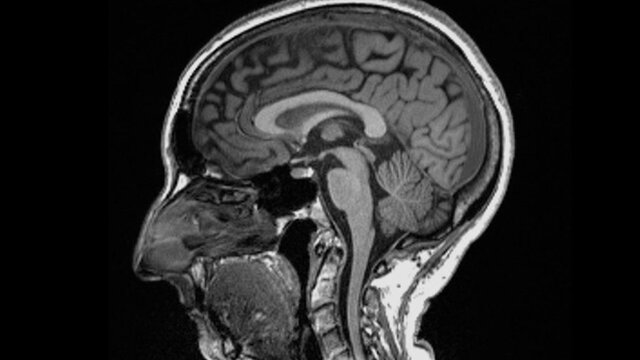

به گزارش خبرگزاری دانا، متخصصان در بررسی های خود تفاوت های قابل توجهی در اسکن MRI افراد، قبل و بعد از ابتلا به بیماری کووید-۱۹ پیدا کردند.

به گزارش خبرگزاری دانا، متخصصان در بررسی های خود تفاوت های قابل توجهی در اسکن MRI افراد، قبل و بعد از ابتلا به بیماری کووید-۱۹ پیدا کردند.به گفته آنان حتی پس از ابتلا به نوع خفیف بیماری، اندازه کلی مغز اندکی کوچک شده و ماده خاکستری کمتری در بخشهای مربوط به بویایی و حافظه وجود داشته است.

در این بررسی سوابق پزشکی ۵۰۰ هزار نفر از حدود ۱۵ سال قبل و داده های مربوط به اسکن آنها قبل از همه گیری، مورد مطالعه قرار گرفت و در دوران همه گیری دوباره از تعدادی از این بیماران اسکن مغزی گرفته شد که این شرکت کنندگان شرایط ذیل را داشتند:

- اندازه کلی مغز افراد آلوده به کروناویروس بین ۰.۲ تا ۲ درصد کوچک شده بود.

- از میزان ماده خاکستری در نواحی بویایی مرتبط با بویایی و مناطق مرتبط با حافظه کاسته شده بود.